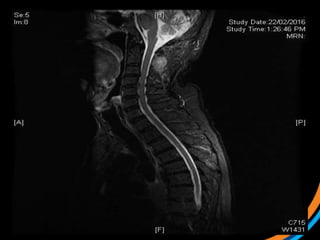

Case study 2 (Patient 003)

• 37 F, ECOG 0

• Met cervical Ca

• On PDL1 clinical trial

• Symptomatic L1 met s/p stabilisation

• For post-op SBRT

 1) Review the images

 2) Target the lesion

*Post-op targeting is more subjective. Post-op consensus guidelines likely to

• #36 T1c and T2

• #37 Post-instrumentation diagnostic CT